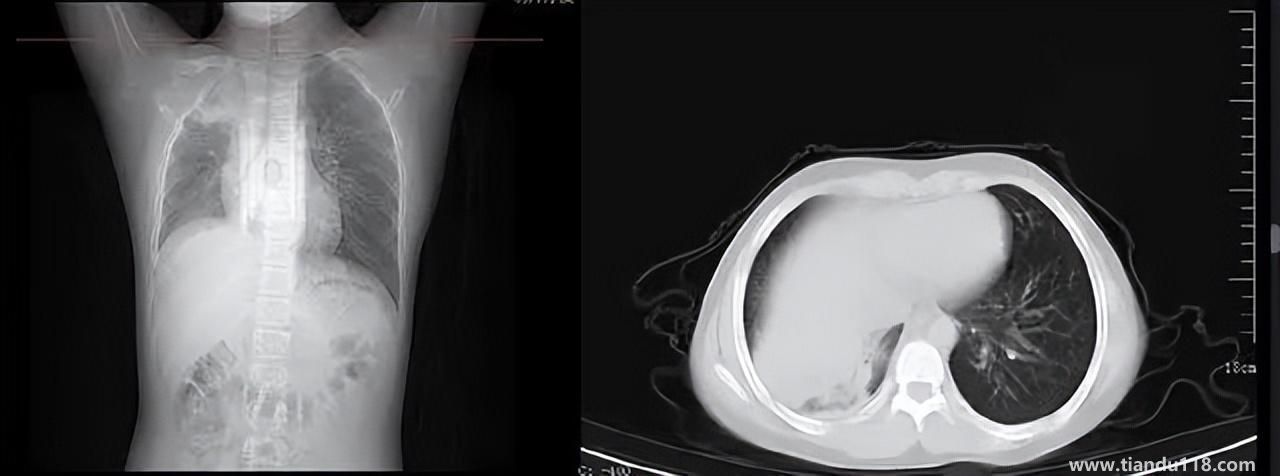

3個(gè)辦法可提前預(yù)警白肺(咋預(yù)防“白肺”) 3個(gè)辦法可提前預(yù)警白肺(咋預(yù)防“白肺”)家里有老人,擔(dān)心出現(xiàn)“大白肺”、“沉默型缺氧”等情況,具體如何應(yīng)對,提前預(yù)警?近日,大象新聞接到諸多咨詢。針對這些問題,大象新聞?dòng)浾咦隽硕喾讲稍L。什么是白肺?對... 小編 2022-12-28 693

白肺與原始毒株和疫苗接種沒關(guān)系(國家衛(wèi)健委表示) 白肺與原始毒株和疫苗接種沒關(guān)系(國家衛(wèi)健委表示)從近期的公眾反映情況看,有的新冠病毒感染者在就診過程中發(fā)現(xiàn)了肺炎或者是CT出現(xiàn)了白肺的現(xiàn)象,有網(wǎng)友認(rèn)為,出現(xiàn)這種情況可能是跟感染了原始毒株或者接種疫苗有... 小編 2022-12-28 530

男孩咳嗽發(fā)熱在家硬扛成白肺(醫(yī)生表示以下幾種情況別硬“扛”) 男孩咳嗽發(fā)熱在家硬扛成白肺(醫(yī)生表示以下幾種情況別硬“扛”) 近日,一名12歲男孩咳嗽一周不就醫(yī),一側(cè)肺部“扛”成了“白肺”?!氨е鴥e幸心理一直在家硬‘扛’,沒想到‘扛’出這么重的?。 焙⒆蛹议L悔不... 小編 2022-12-28 939

為何有人出現(xiàn)“白肺”?專家回應(yīng)和疫苗接種無關(guān) 為何有人出現(xiàn)“白肺”?專家回應(yīng)和疫苗接種無關(guān)國務(wù)院聯(lián)防聯(lián)控機(jī)制12月27日召開新聞發(fā)布會(huì),針對有媒體提問稱,從近期公眾的反映情況看,有的新冠病毒感染者在就診過程中發(fā)現(xiàn)了肺炎或者是CT出現(xiàn)了“白肺”的現(xiàn)... 小編 2022-12-27 817

感染新冠會(huì)變白肺?醫(yī)生:有年輕病例 感染新冠會(huì)變白肺?醫(yī)生:有年輕病例感染新冠會(huì)變白肺嗎?對此,有專家表示,造成“白肺”情況有很多種,感染新冠只是一種可能。少量患者肺有滲液 ,咳嗽不會(huì)引發(fā)白肺,有年輕人病例。... 小編 2022-12-27 608